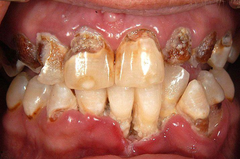

Meth mouth

-generalized extensive destruction of tooth surface -meth use